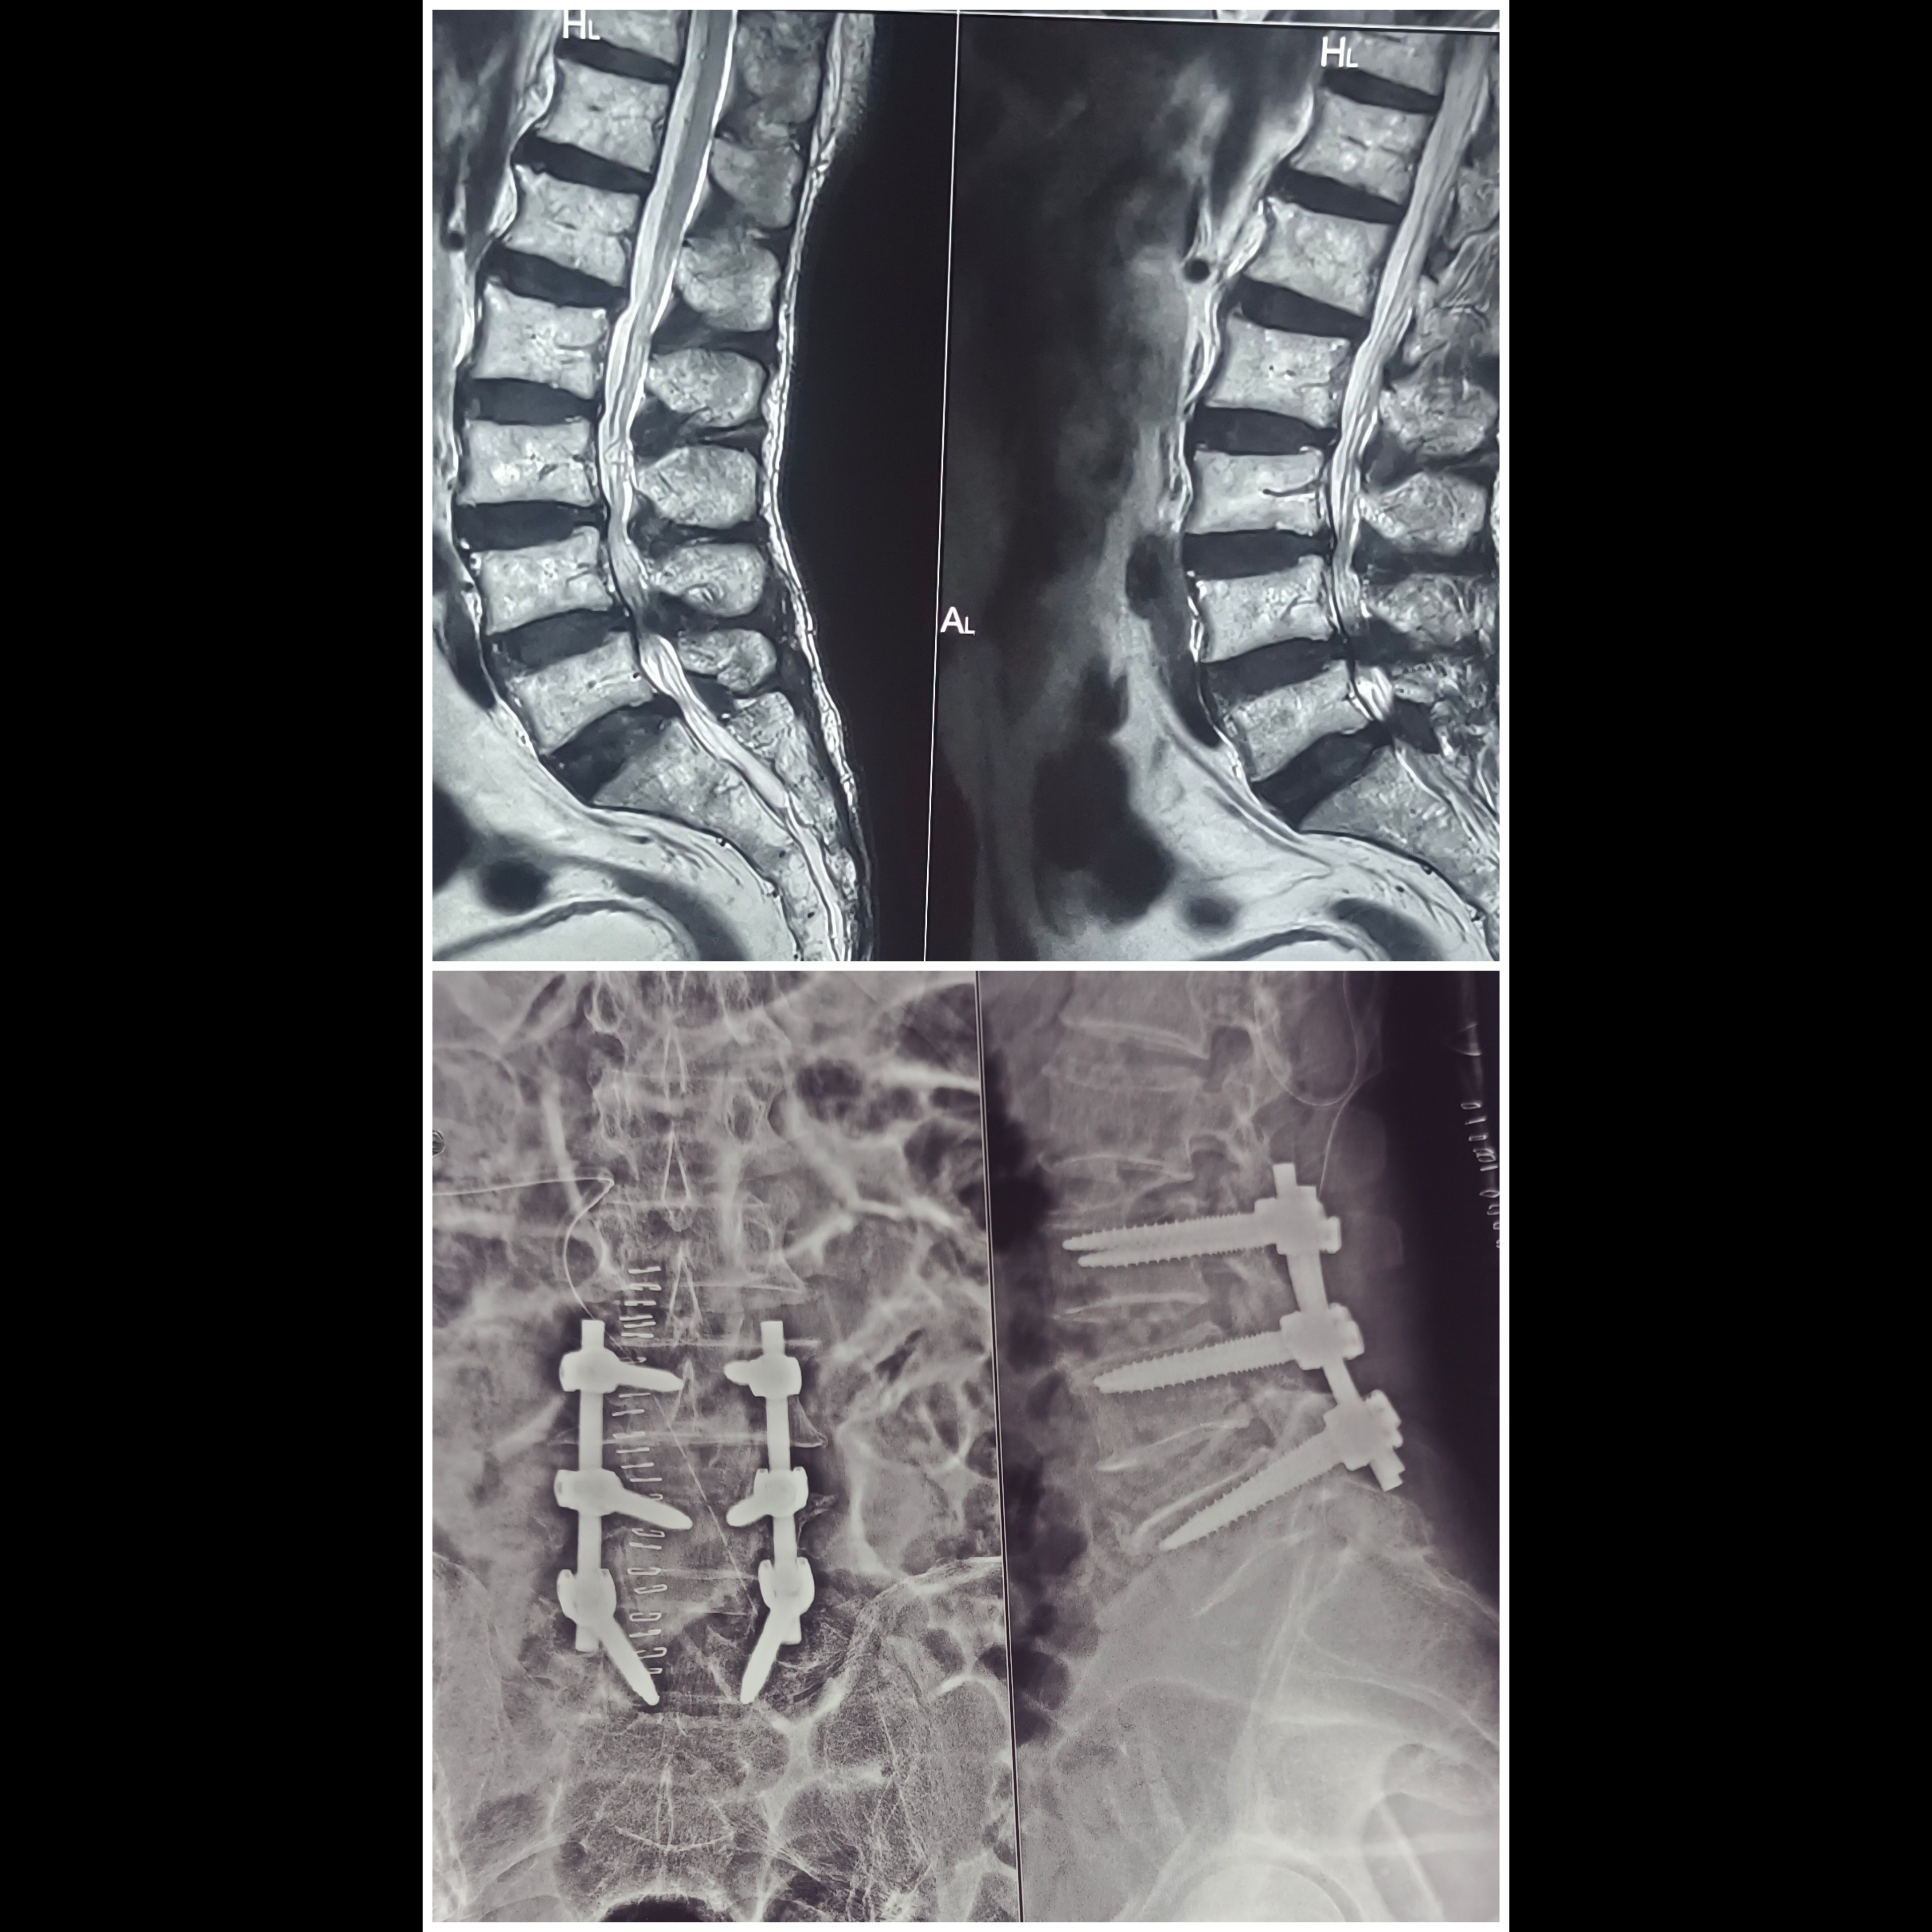

Are you searching for Spine Surgery Specialist in Pune ? Spine Surgery Doctor in Pune ? Spine Surgery Specialist In Shivaji Nagar ? Spine Canal Stenosis treatment in Pune ? Spine Fixation Surgeon in Pune ? Meet Dr. Nitish Agarwal Best Spine Surgeon in Pune, Shivaji Nagar, Deccan, Kothrud, Erandwane, Dattawadi, Swargate, FC road, Karve Road. This patient was having Severe Low Back Pain since 10 Years. He is also having Severe leg Pain, Both Lower limb tingling since 10 Years. He is having L3-4, L4-5 Disc Prolapse With Severe Nerve Root Compression with Spinal Canal Stenosis with Facetal Arthropathy diagnosed by MRI. We did L3-L4, L4-L5 Spine Fixation Surgery by stabilizing his Spine with Titanium Screws and Rods. We also remove disc and freed the Nerve Roots to relieve Leg pain and Tingling sensation in Legs. Patient starts walking from next day of Surgery. Now he is Walking Pain Free and Doing Regular exercises.